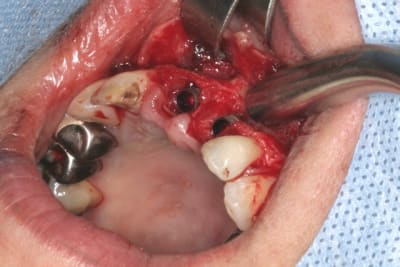

un autre cas EII MCI sur 11/21...mais en photos (j'ai aussi la vidéo, faut que je la passe sur youtube)

1 t869zn - Eugenol

2 v0ltek - Eugenol

3 rz5ncz - Eugenol

4 k166af - Eugenol

5 gkyzlc - Eugenol

6 fb5vql - Eugenol

7 h4oidg - Eugenol

8 q7vqsz - Eugenol

9 lxiqek - Eugenol

10 x3icur - Eugenol

11 sesulr - Eugenol

15 tsavm7 - Eugenol

17 rcd7v0 - Eugenol

19 vzirgi - Eugenol

23 gy4ot5 - Eugenol

24 gnhyk0 - Eugenol

27 xb8gd5 - Eugenol

32 lelywv - Eugenol

36 qq6o4s - Eugenol

38 ovoosl - Eugenol